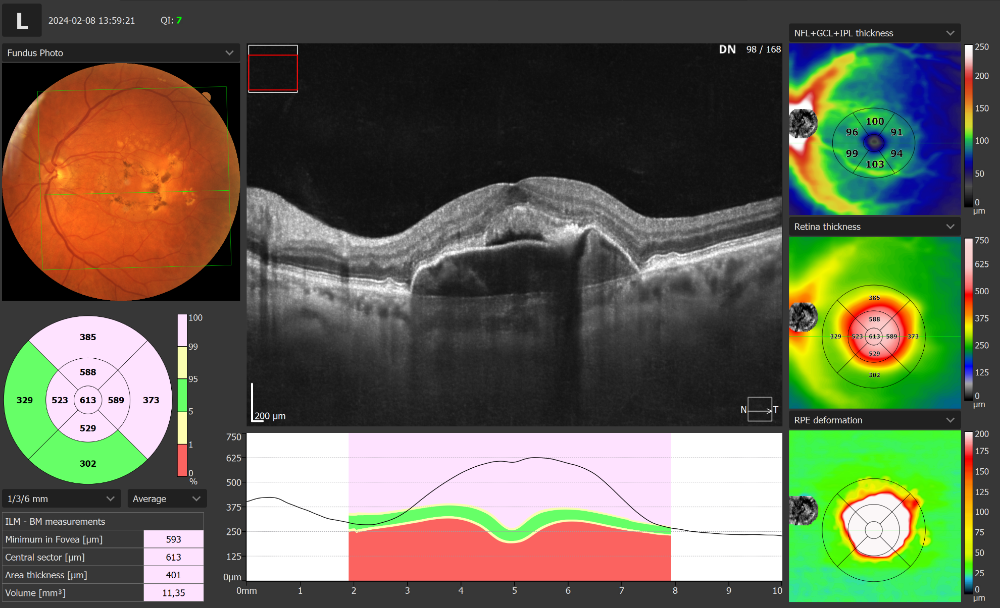

Ce sont ces tomographies OCT de très haute définition et des analyses complètes des couches rétiniennes, du segment antérieur, combinées à une imagerie du fond d’œil rendant l’examen plus polyvalent que jamais. L'OCT REVO HR offre une caméra de fond d’œil non mydriatique intégrée de 12,3 MP capable de capturer des images couleurs détaillées et de très haute qualité

Une caméra couleur de 12,3 MP est intégrée à notre appareil All in One OCT capable de capturer des images couleurs détaillées de très haute qualité.

L'OCT REVO HR avec une vitesse de balayage de 130 000 A-scan/sec utilise des technologies de pointe et offre une remarquable simplicité d'utilisation. Il répond à toutes les exigences d'un OCT moderne.